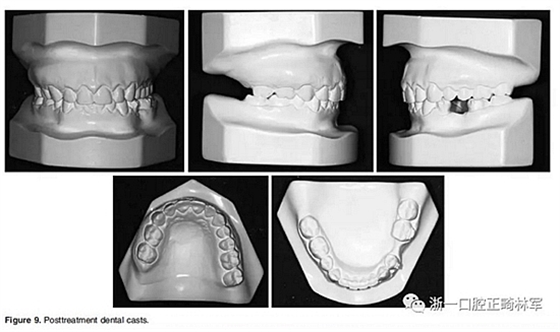

在治療結(jié)束時,面部基本對稱(Figure 7)。上中線與面中線重合,下中線向左偏0.5mm,傾斜的合平面得到矯正,獲得了良好的咬合關(guān)系,具有正常的覆合和覆蓋,留下7mm的空間用于植入左下前磨牙(Figure 8、9)。

全景片顯示牙根平行度良好、無吸收。此外,在左下第二前磨牙的區(qū)域獲得了用于植入種植體修復的良好空間。頭顱側(cè)位片和疊加顯示,上下切牙傾斜度以及前后和垂直向位置的變化也很大(Figure 10、11; Table 1)。